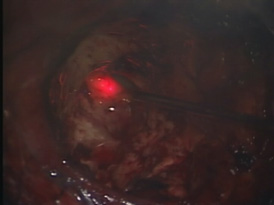

蛍光診断(光線診断) PhotoDiagnosis(PD)

脳腫瘍、特に神経膠腫(glioma)では摘出術中に正常の脳組織との区別が難しいことがしばしばあります。そのような場合には、脳腫瘍かと思って切除したら大事な正常脳組織であったり、また正常組織かと思われた部分が脳腫瘍の一部であるということが術後のMRI検査でわかるということもあります。これを防ぐために用いられる方法が蛍光診断です。

手術前にアミノレブリン酸というお薬をブドウ糖に溶かして内服していただきます。そして手術中に脳腫瘍のあたりに青い光を当てると腫瘍だけが赤く光って見えます。

(左図)腫瘍を摘出後

(右図)青い光を当て、残存腫瘍だけが赤く光る。

この赤く光った部分を摘出すれば腫瘍の全摘出が完了します。